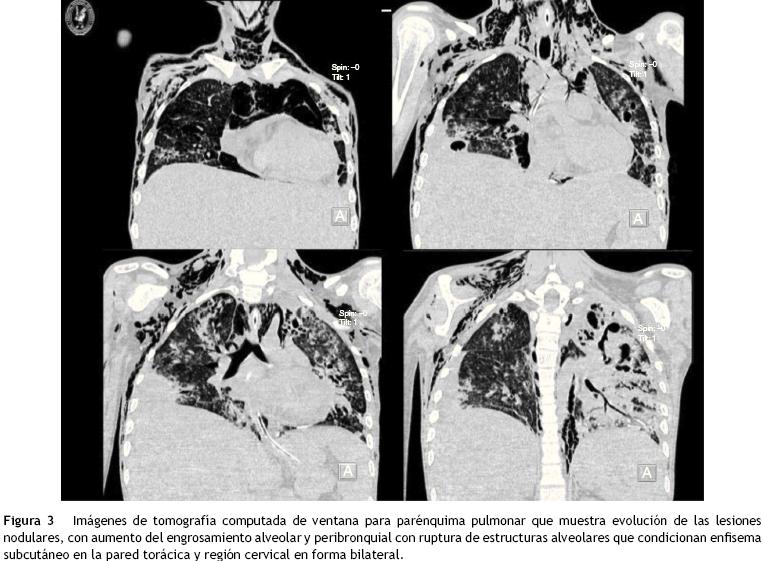

La tomografía de mediastino muestra disección por gas a través de las masas musculares, predominantemente en la región cervical, a nivel del tórax y de predominio axilar. En los segmentos inferiores se observa cómo el aire está prácticamente dibujando todo el trayecto de la aorta. Hay derrame pleural, predominantemente en el lado derecho, y el hígado se encuentra aumentado de tamaño (fig. 3). En la región media hay una diástasis de los rectos y cambios por la ileostomía realizada (fig. 4).